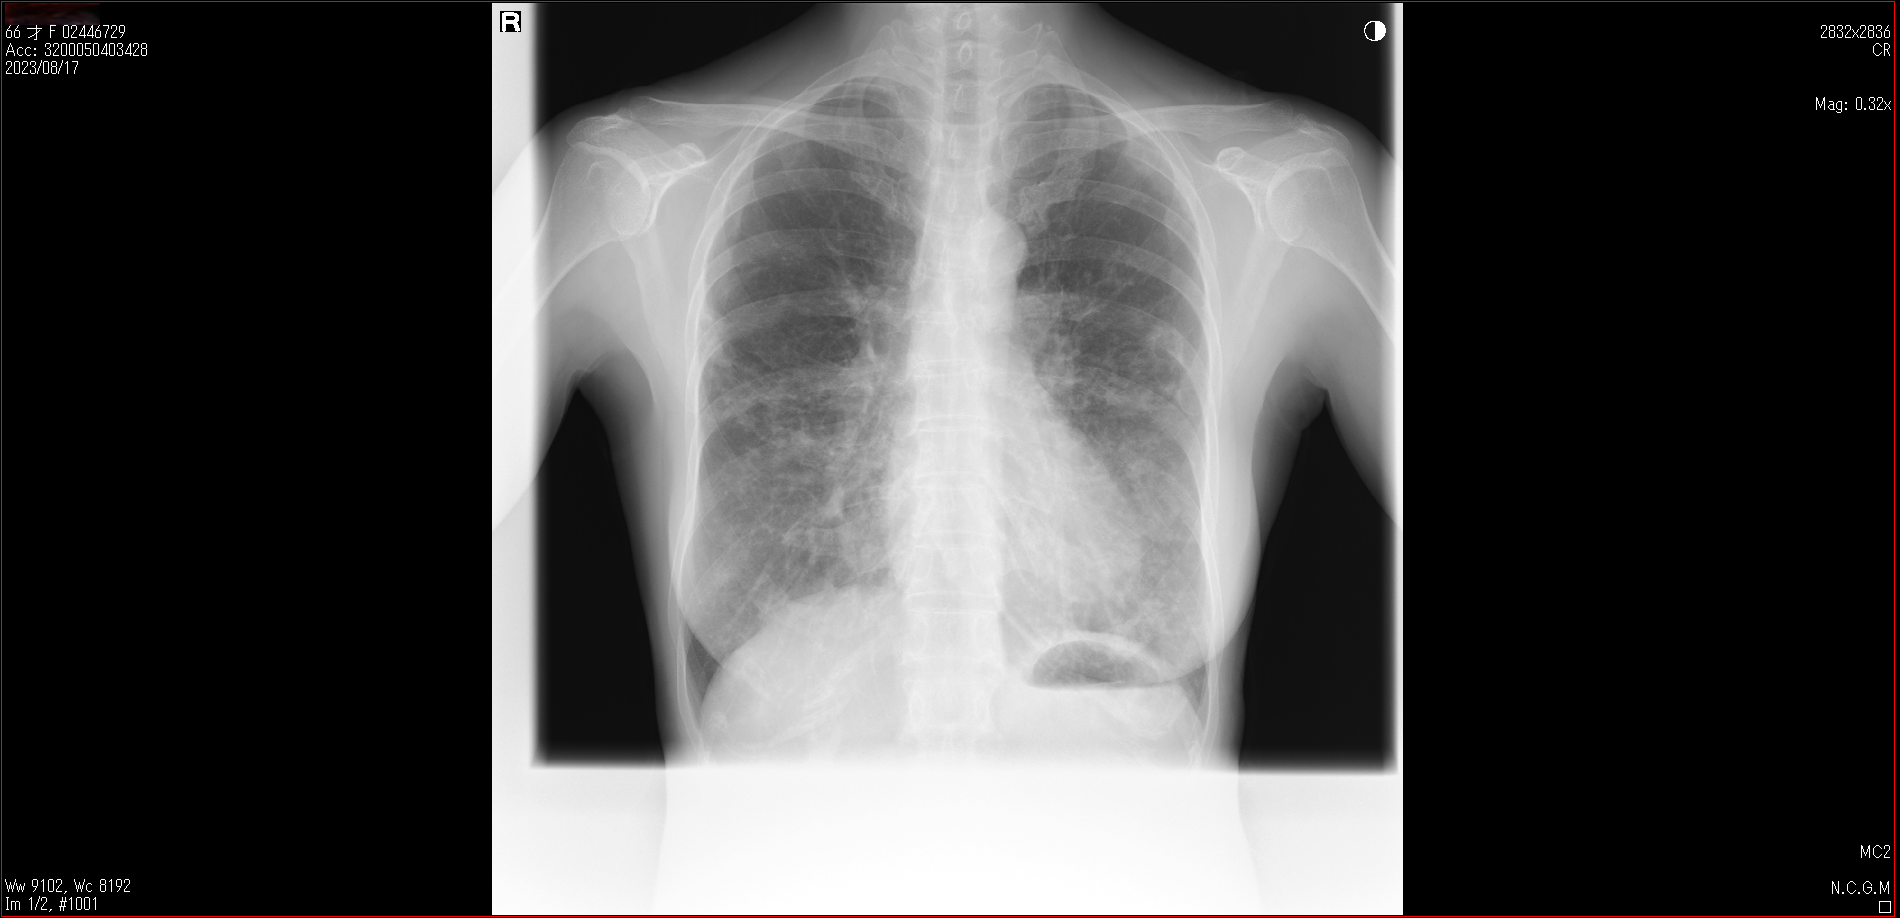

- 2023.08.17 肺炎後の要観察(2)(国立系病院)